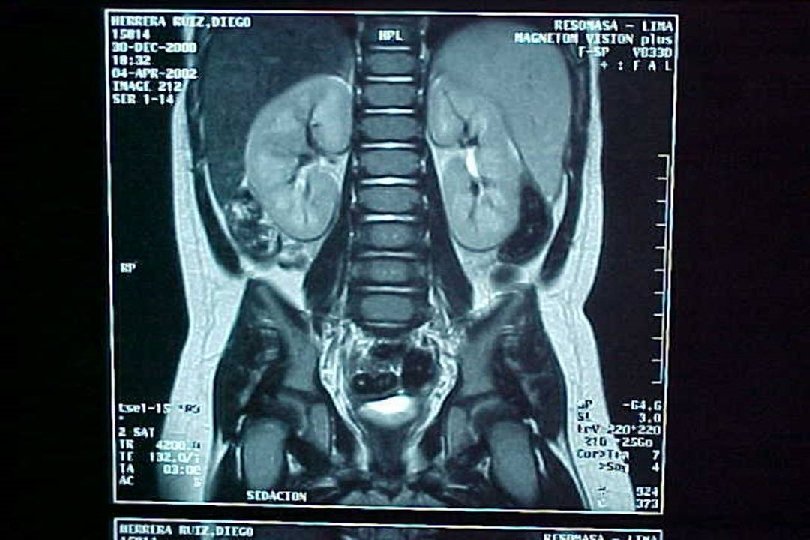

SECUENCIA DE IMAGEN o ECOGRAFIA. o CISTOURETROGRAFIA RETROGADA POST MICCIONAL. o PIELOGRAFIA ENDOVENOSA o GAMMAGRAFIA RENAL CON DMSA-TC 99. o RADIORENOGRAMA o UROGRAFIA POR RMN o TAC HELICOIDAL o ENDOSCOPIA VIRTUAL